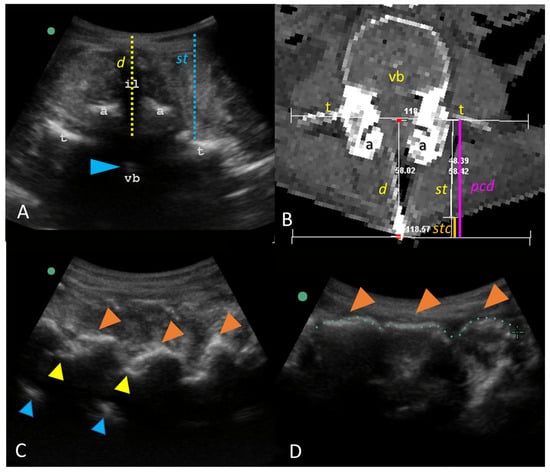

2.3. Visual Guidance of Needle Insertion

2.4. Needle Insertion